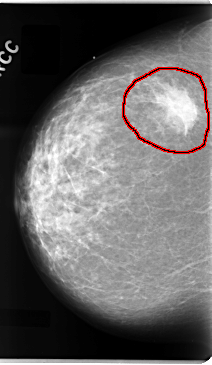

C_0094_1.RIGHT_CC

RIGHT_CC LINES 4736 PIXELS_PER_LINE 2744 BITS_PER_PIXEL 12 RESOLUTION 50 OVERLAY

FILE: C_0094_1.RIGHT_CC.OVERLAY

TOTAL_ABNORMALITIES 1

ABNORMALITY 1

LESION_TYPE MASS SHAPE IRREGULAR MARGINS ILL_DEFINED

ASSESSMENT 5

SUBTLETY 5

PATHOLOGY MALIGNANT

TOTAL_OUTLINES 1

BOUNDARY